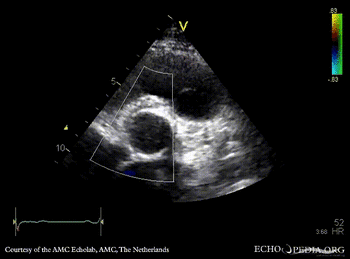

Davids procedure

Courtesy of: AMC Echolab, AMC, The Netherlands

PSAX: native aortic valve and prosthesis in ascending aorta PSAX with Color Doppler